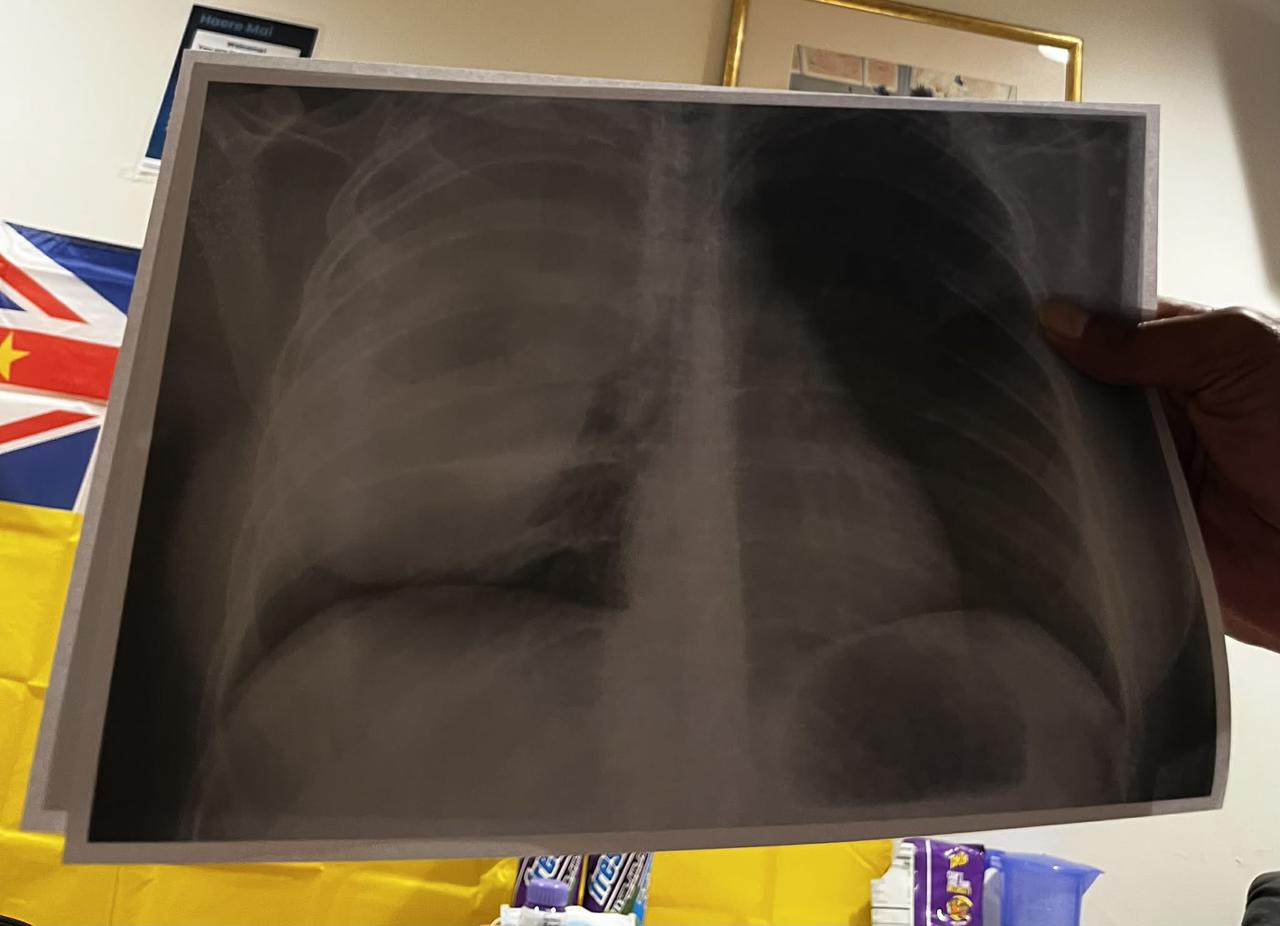

What started as a sore back quickly became a frightening struggle to breathe. At Middlemore Hospital, doctors found a large mass pressing on her heart and lungs, leaving her with almost no space to breathe. She was urgently transferred to Auckland Hospital at 2am and spent over a week in ICU fighting to stabilize.

small update: had a quick xray too look at how things are going which the mass is still pretty big but there has been shrinkage & doctors said they will have a plan by next week just been doing a lot of resting these past couple of days getting my strength back.